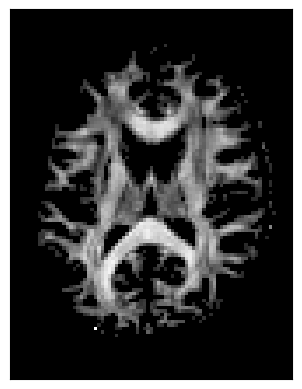

# Show FA slice

plt.figure()

plt.imshow(FA[:, :, sli].T, origin='lower',cmap='magma')

plt.title('FA (DTI) — middle slice')

plt.colorbar(label='FA')

plt.axis('off'); plt.show()

../../_images/452110d8e86d9c40d6448e39ba2d095c461cd3550edd968031bbe4682474f0f2.png